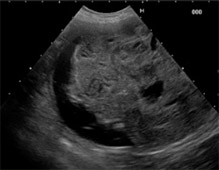

検査:腹部超音波検査にて肝臓内側右葉に直径約12cm大の肝臓腫瘍が認められました。また、胆のうに重度の胆泥の貯留を認めました。

治療:飼い主様の希望により、肝臓腫瘍摘出手術と胆嚢切除手術行いました。肝臓腫瘍摘出は特に血管系の処理が重要で基本的な結紮技術はもちろん、超音波乳化吸引装置や血管シーリング装置などを駆使し血管を一つずつ処理して行きます。